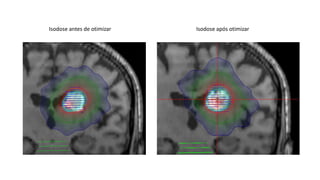

Isodose antes de otimizar Isodose após otimizar

Como mudou o índice de conformidade após otimização

Ambos índices tiveram melhorias. O índice 1 (Paddick) é melhor quanto mais perto de 1.00.

O índice de 2 (Jackie, et. al.) é perfeito quando seja 0.0, ele mede a distância média entre a isodose

de prescrição e a borda do alvo (PTV neste caso).

Isodose de 60% otimizada em relação do PTV